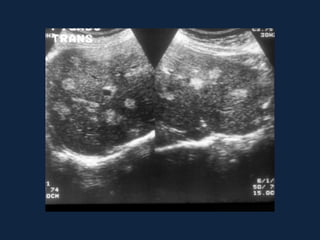

Distribuição perivascular

• Esquistossomose

– Fibrose periportal

– Hipertensão pré-sinusoidal

– US: Aumento da ecogenicidade

periportal (“céu estrelado”)

– TC:

• SC: Bandas hipodensas

periportais

• CC: contrastação tardia

– RNM:

• T1: Bandas fibrosas 

• T2: Bandas fibrosas 

• Contraste tardio

ESQUISTOSSOMOSE MANSÔNICA

• Intensa reação

inflamatória que

resulta em fibrose

periportal.

• Atrofia do lobo direito,

hipertrofia do lobo

esquerdo e

hipertensão portal.